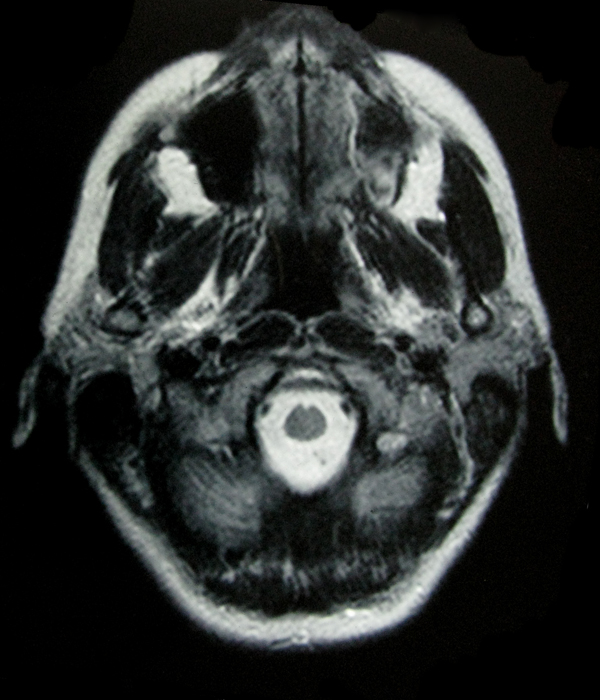

- My Brain in 2009